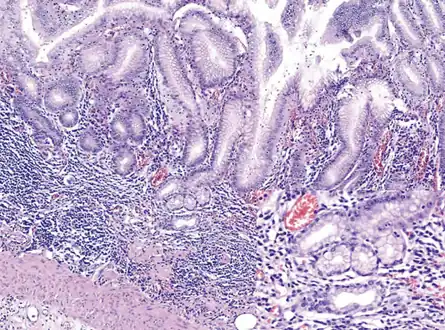

Environmental metaplastic atrophic gastritis (EMAG) is due to environmental factors, such as diet and H. pylori infection. EMAG is typically confined to the body of the stomach. Patients with EMAG are also at increased risk of gastric carcinoma.

Autoimmune metaplastic atrophic gastritis (AMAG) is an inherited form of atrophic gastritis characterized by an immune response directed toward parietal cells and intrinsic factor.[6] The presence of serum antibodies to parietal cells and to intrinsic factor are characteristic findings. The autoimmune response subsequently leads to the destruction of parietal cells, which leads to profound Achlorhydria (and elevated gastrin levels). The inadequate production of intrinsic factor also leads to vitamin B12 malabsorption and pernicious anemia. AMAG is typically confined to the gastric body and fundus.

Achlorhydria induces G cell (gastrin-producing) hyperplasia, which leads to hypergastrinemia. Gastrin exerts a trophic effect on enterochromaffin-like cells (ECL cells are responsible for histamine secretion) and is hypothesized to be one mechanism to explain the malignant transformation of ECL cells into carcinoid tumors in AMAG.